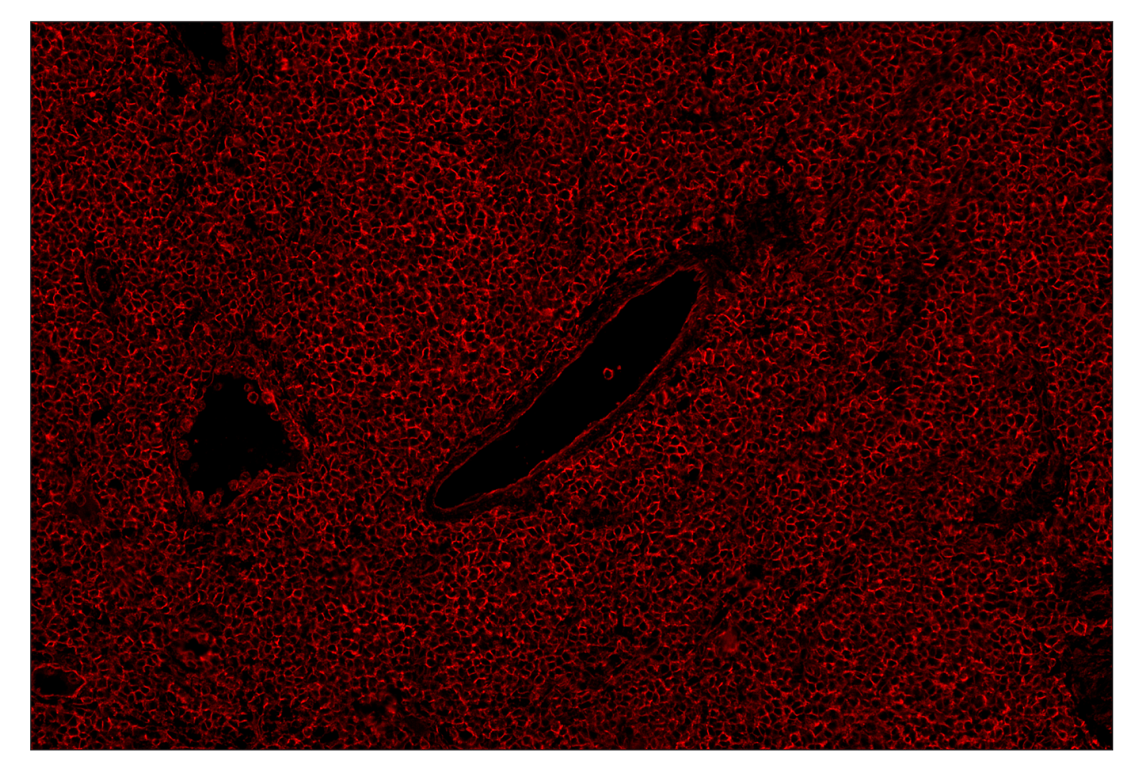

SignalStar™ multiplex immunohistochemical analysis of paraffin-embedded human tonsil using MHC Class I (EMR-8) & CO-0082-647 SignalStar™ Oligo-Antibody Pair #24698 (red). All fluorophores have been assigned a pseudocolor, as indicated. Staining was performed on the BOND RX autostainer by Leica Biosystems.

Immunohistochemistry Image 4: MHC Class I (EMR8-5) & CO-0082-647 SignalStar<sup>™</sup> Oligo-Antibody Pair